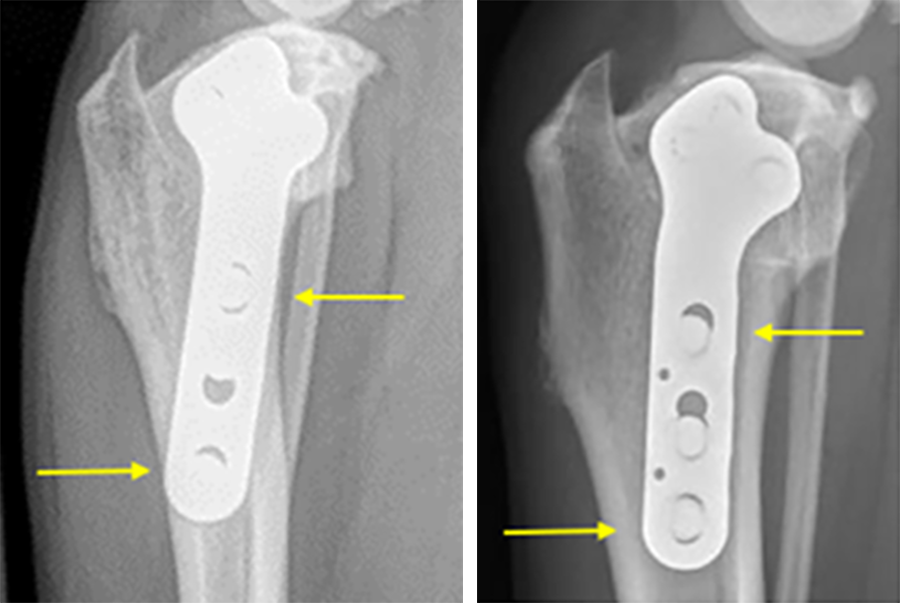

The currently available DePuy Synthes 3.5 mm TPLO plate is generally applied at a slight angle relative to the mechanical axis of the tibia. While this has proven to be an ideal angle from a compression standpoint, there may be instances where the distal‐most screw is close to the cranial cortex of the tibia and the third most distal screw is close to the caudal cortex. In extreme cases these screw locations could cause increased bone stress in those regions.

The newly innovated implant, 3.5 mm TPLO with Advanced Radial Compression (ARC), locates these screws closer to the center of the bone while preserving the clinically‐proven angle of compression.

The ARC TPLO plate provides continuous, controlled, and directed compression across the osteotomy via a unique system of holes that serves to translate and rotate the plate simultaneously during compression. The resultant direction of compression has been designed to match that of the DPS standard TPLO plate, which is clinically proven to provide excellent healing and improved resistance to rock‐back.